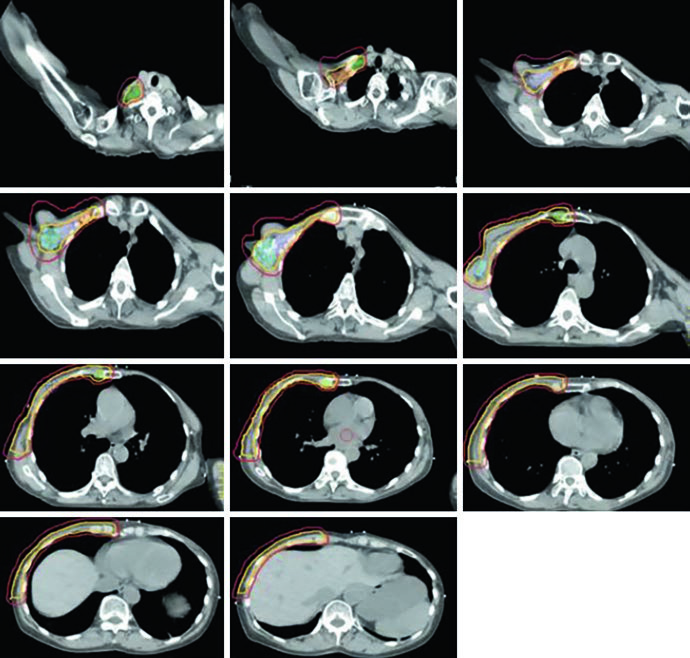

Conventional 3D conformal planning for regional nodal irradiation typically employs a three-beam arrangement: a medial en face electron beam matched to two opposing lateral tangent fields. This classic configuration provides adequate chest wall and IMN coverage with the electron beam, while the tangents treat the lateral breast/chest wall volume and the lower axillary nodes. The main advantage of this technique is its simplicity and reproducibility, although dosimetric homogeneity at the electron-photon junction remains a constant concern.

The supraclavicular field is planned separately as an anterior oblique or AP field, covering the level III and supraclavicular nodes. Figure 12.7 shows the coronal view of this field with the nodal targets overlaid — the junction between the supraclavicular field and the inferior tangents is one of the critical points of treatment, where overdose or underdose can occur if the geometry is not precise. The half-beam block technique (asymmetric jaw) minimizes divergence at the junction and reduces the risk of dose overlap.

For the tumor bed boost, an en face electron field with a custom cutout is typically used. Figure 12.8 demonstrates this setup in a 3D view: the electron field (blue) encompasses the tumor bed (maroon), surgical clips (light green), and the lumpectomy scar (gray). Electron energy selection depends on bed depth — in practice, 9–12 MeV covers most cases, following the rule that the 80% isodose reaches a depth in centimeters of approximately $E/3$, where $E$ is the energy in MeV.